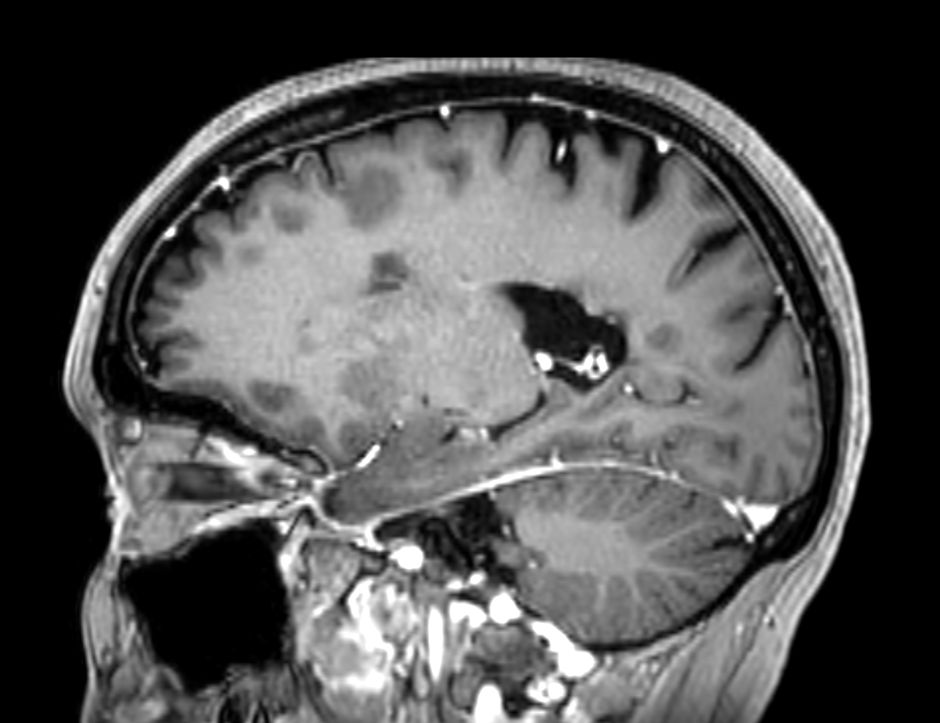

Multiple Sclerosis versus TIA

Standardized Multiple Slerosis MRI protocols typically require long scan times. Addition of Compressed SENSE enables faster exams, without compromise in image quality1. SWIp sequence has a high sensitivity to enhance contrast for deoxygenated (venous) blood or calcium deposits. This may help, when used in combination with other clinical information, in the diagnosis of various neurological pathologies. 3D (BrainVIEW) lets you acquire high resolution data in multiple directions in one scan. Isotropic voxel size enables reformats in any plane without loss of resolution.

3D T1w FFE +Gado Compressed SENSE

3D T1w FFE (reformat) +Gado Compressed SENSE

-